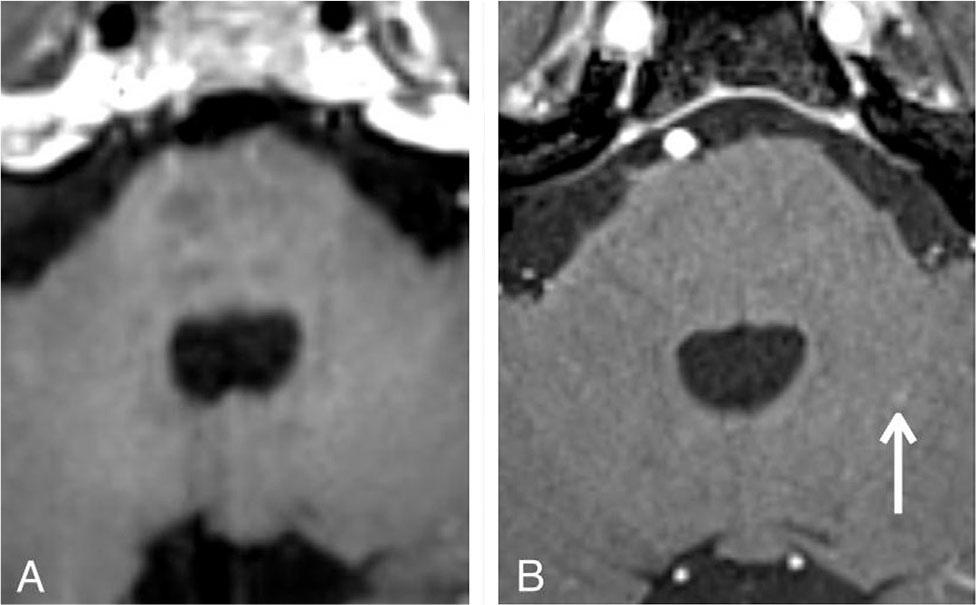

Figure 7

A 62-year-old lung cancer patient with a false-positive lesion in the left temporal lobe (white arrow). Axial contrast-enhanced 3D T1-weighted SPACE (A) and contrast-enhanced 3D T1-weighted VIBE (B). A false-positive lesion is a partial hyperintensity of a blood vessel which mimics enhancing brain metastasis on contrast-enhanced 3D T1-weighted SPACE (A). The linear hyperintensity continues as a vascular structure on contrast-enhanced 3D T1-weighted VIBE (B).

Both sequences truly missed at least one parenchymal enhancing lesion. The SPACE sequence truly missed one parenchymal enhancing lesion in one patient (Figure 5). The VIBE sequence truly missed seven parenchymal enhancing lesions in six patients (Figure 6). There were three false-positive lesions on SPACE sequence and three false-positive lesions on VIBE sequence. These false-positive lesions were probably leptomeningeal enhancement or vascular structure that was mistakenly counted as a parenchymal enhancing lesion on one of the sequences (Figure 7).

Similar with previous studies [23, 26], this study found one false-positive lesion on the SPACE due to the scattering regions of short-segment vascular enhancement (Figure 7). On SPACE sequence alone, it is difficult to differentiate the enhancing metastasis from the partial hyperintensity in slow flow blood vessel when the continuity with the adjacent tubular-shaped vascular structure is lost. A study has suggested that concurrent review of 3D T1-weighted gradient-echo-based sequence (e.g., MPRAGE or VIBE) and 3D T1-weighted fast spin-echo-based sequence (e.g., SPACE) was helpful for differentiating the nature of the enhancing foci by showing their continuity with vascular structures [26]. We confirmed that the rest of the enhancing lesions detected on SPACE sequence were not false-positive lesions by head-to-head comparison of the lesions on both VIBE and SPACE sequences. Some investigators proposed additional options such as motion-sensitized magnetization prepared pulse and its variants to improve vascular signal suppression at the expense of higher susceptibility to motion due to longer acquisition time [30, 31, 32].